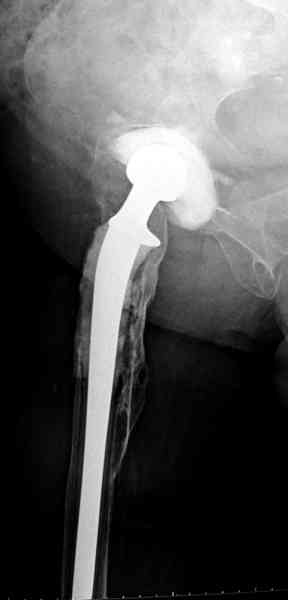

Наглухо ушитая рана с дренажом зажила первично, после чего с больной потерял контакт, и только недавно, через 8 лет я осмотрел её. Она без проблем нагружает на конечность и передвигается с помощью трости. От окончательной операции по реконструкции отказывается, довольная результатом.

Имеются литературные данные, когда спейсер держали не более 6 месяцев, но этот случай бьет все рекорды, может быть для наших людей, обременных финансовыми трудностями, нужна другая шкала оценки сроков нахождения спейсеров.

и последние снимки.